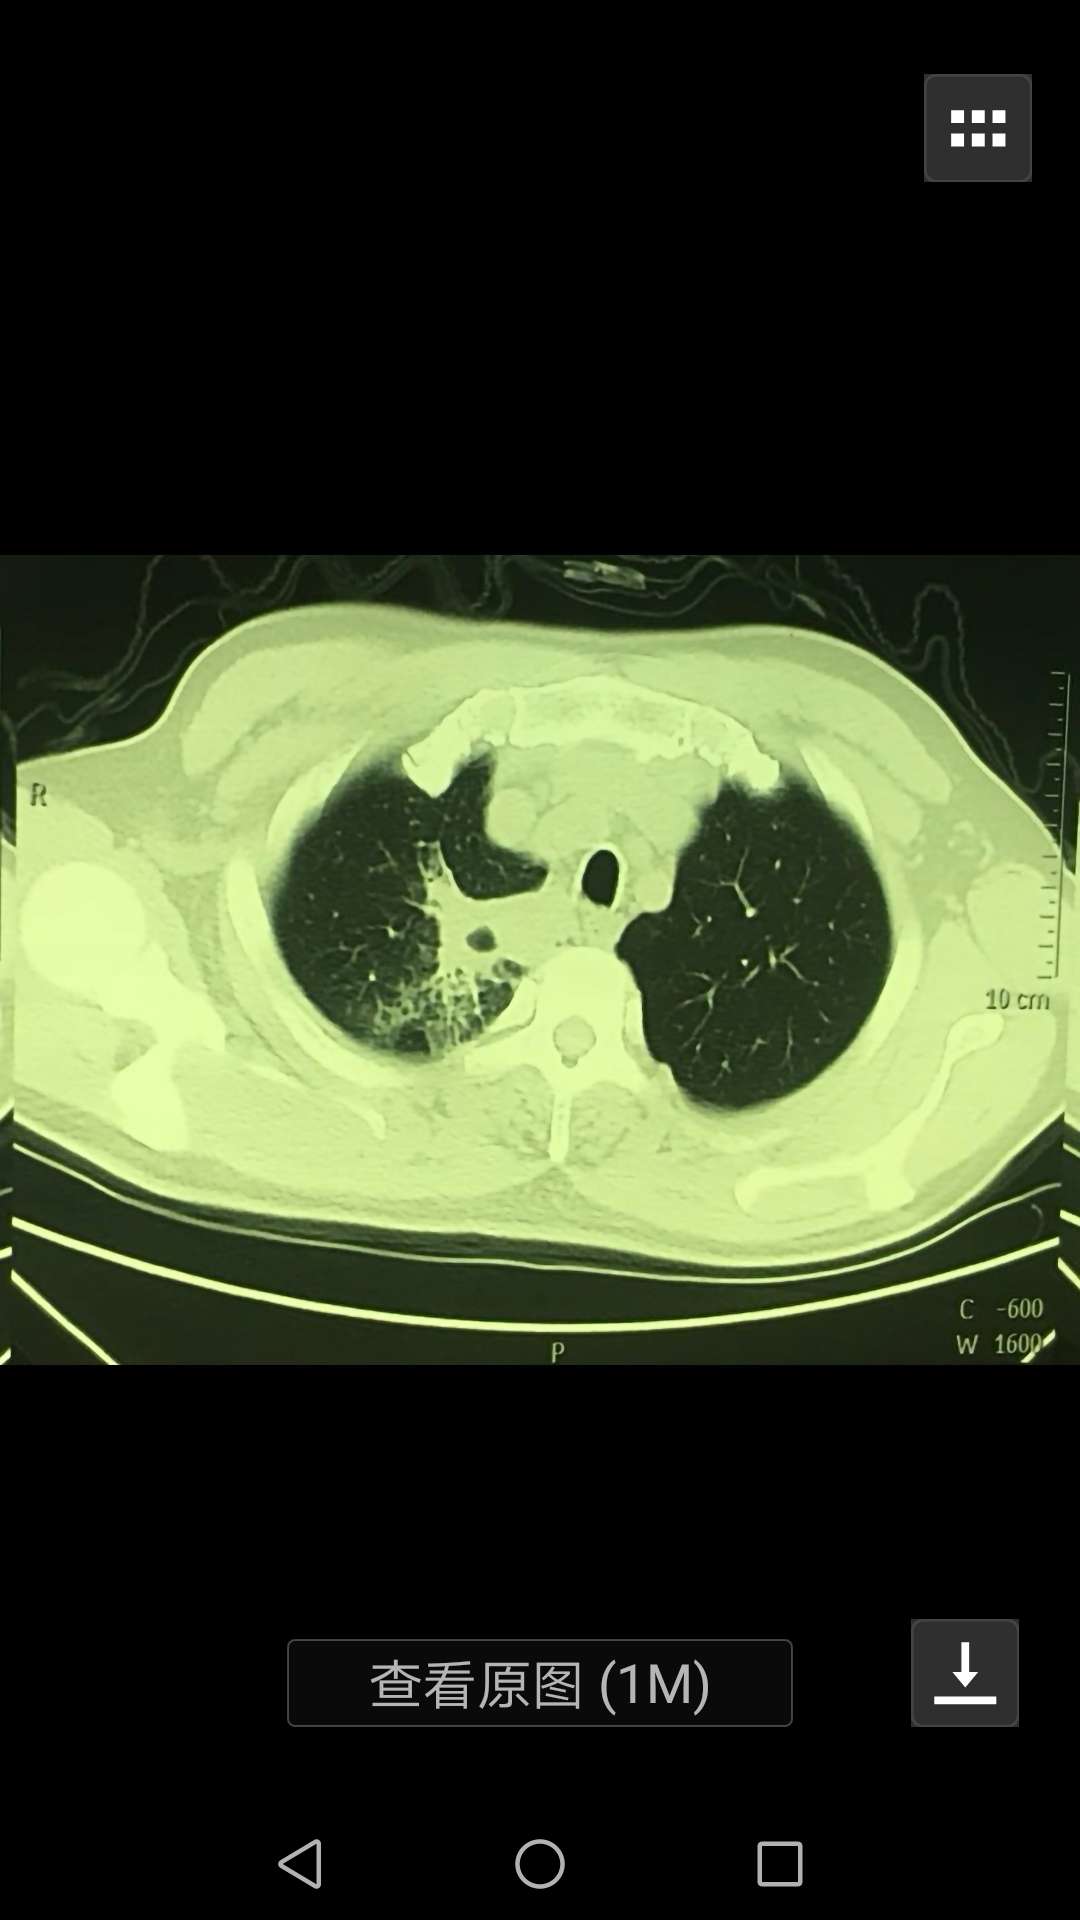

求神医帮忙看片子,能否排除是肺癌的可能

陈波医生结核性脓肿的可能性还是要大于肺癌性脓肿。做了增强CT吗

陈波医生空洞略呈液平,就是底端有条平线,这种更像坏死后产生的液平,肿瘤的一般空洞🐛咬样坑坑洼洼的不平

陈波医生看看这个典型的肺脓肿的空洞,你们家的这个洞已经有了雏形了,那个类三角形的洞的底边后续会更平,形成液平线,这种是感染坏死形成的

陈波医生感染比较快的,有液平的还是感染可能性大,但不能凭借这个完全排除肿瘤的,先好好抗感染看看吸收情况,注意排查结核的感染,有糖尿病吗